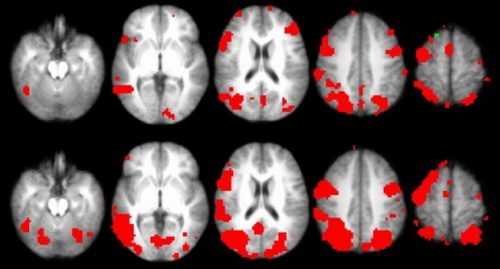

大脑成像发现了与已经遗忘的记忆相对应的激活模式

在这项由大学生进行的研究中,大脑成像发现了与这些学生认为的已经遗忘的记忆相对应的激活模式。美国加利福尼亚州大学欧文分校神经生物学家杰弗里·约翰逊表示:“即使大脑仍保留着被遗忘的记忆,你可能也永远无法访问这些信息。”约翰逊的评论出现在有关这项研究的论文中,研究论文由他联合执笔,刊登在9月9日出版的《神经元》(Neuron)上。

20分钟之后,研究人员再次向参与的学生展示单词表,并要求他们尽可能回想起每一个单词。这种回忆触发了最初的学习模式,整个过程在技术上被称之为“恢复”。记忆力越强,所传递的信号也越强。斯坦福大学记忆研究员安东尼·瓦格纳表示:“在我看来,这项研究最令人兴奋的发现就是皮层复原程度与我们记忆的主观体验强度有关。”瓦格纳并没有参与约翰逊等人的研究。

值得关注的是,在“恢复”程度最低的情况下,参与者有意识回想起的内容降为零,但信号仍然存在。一种可能的情况是,这些学生在他们回想起来的事情上撒了谎。如果不是这种情况,他们的记忆可能继续存在。